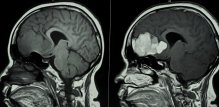

Magnetska rezonancija s kontrastom može uzrokovati migrene